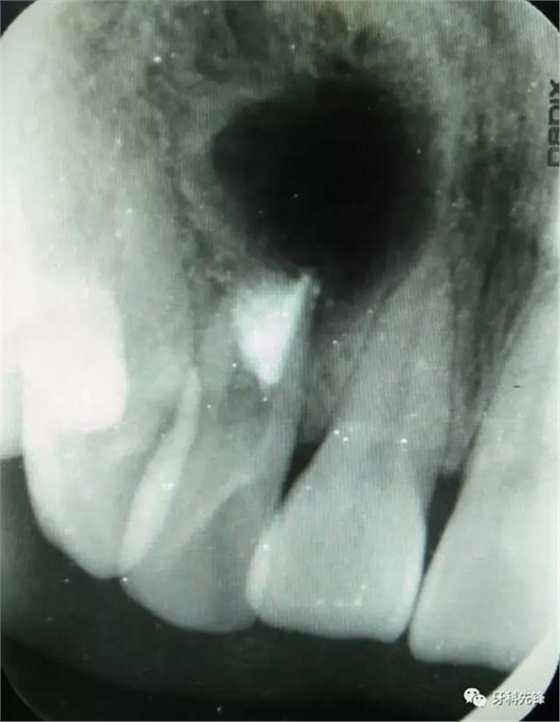

患者、高xx、女、31歲,主訴:右側(cè)上前牙牙冠變色,要求治療。??茩z查:12牙冠成灰褐色。叩診(-)、不松動,x光:12根尖區(qū)有一橢圓形陰影,大小約花生米,囊腔內(nèi)有一致密團塊。約綠豆大小,12根管粗大,根尖孔開放。診斷:含牙囊腫。治療建議:建議摘除囊腫,并試保留12,患者同意治療方案,簽知情同意書。

圖1.術(shù)前的根尖片影像檢查:12根管粗大、根尖未形成。根尖下方有一橢圓形囊腔,囊內(nèi)有牙。